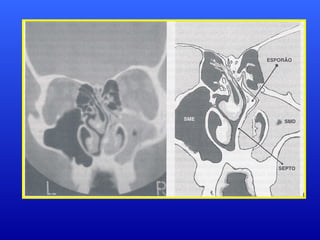

Correlação entre PalatoEscavadoCorrelação entre Palato Escavado e Desvio de Septo Nasal:e Desvio de Septo Nasal: